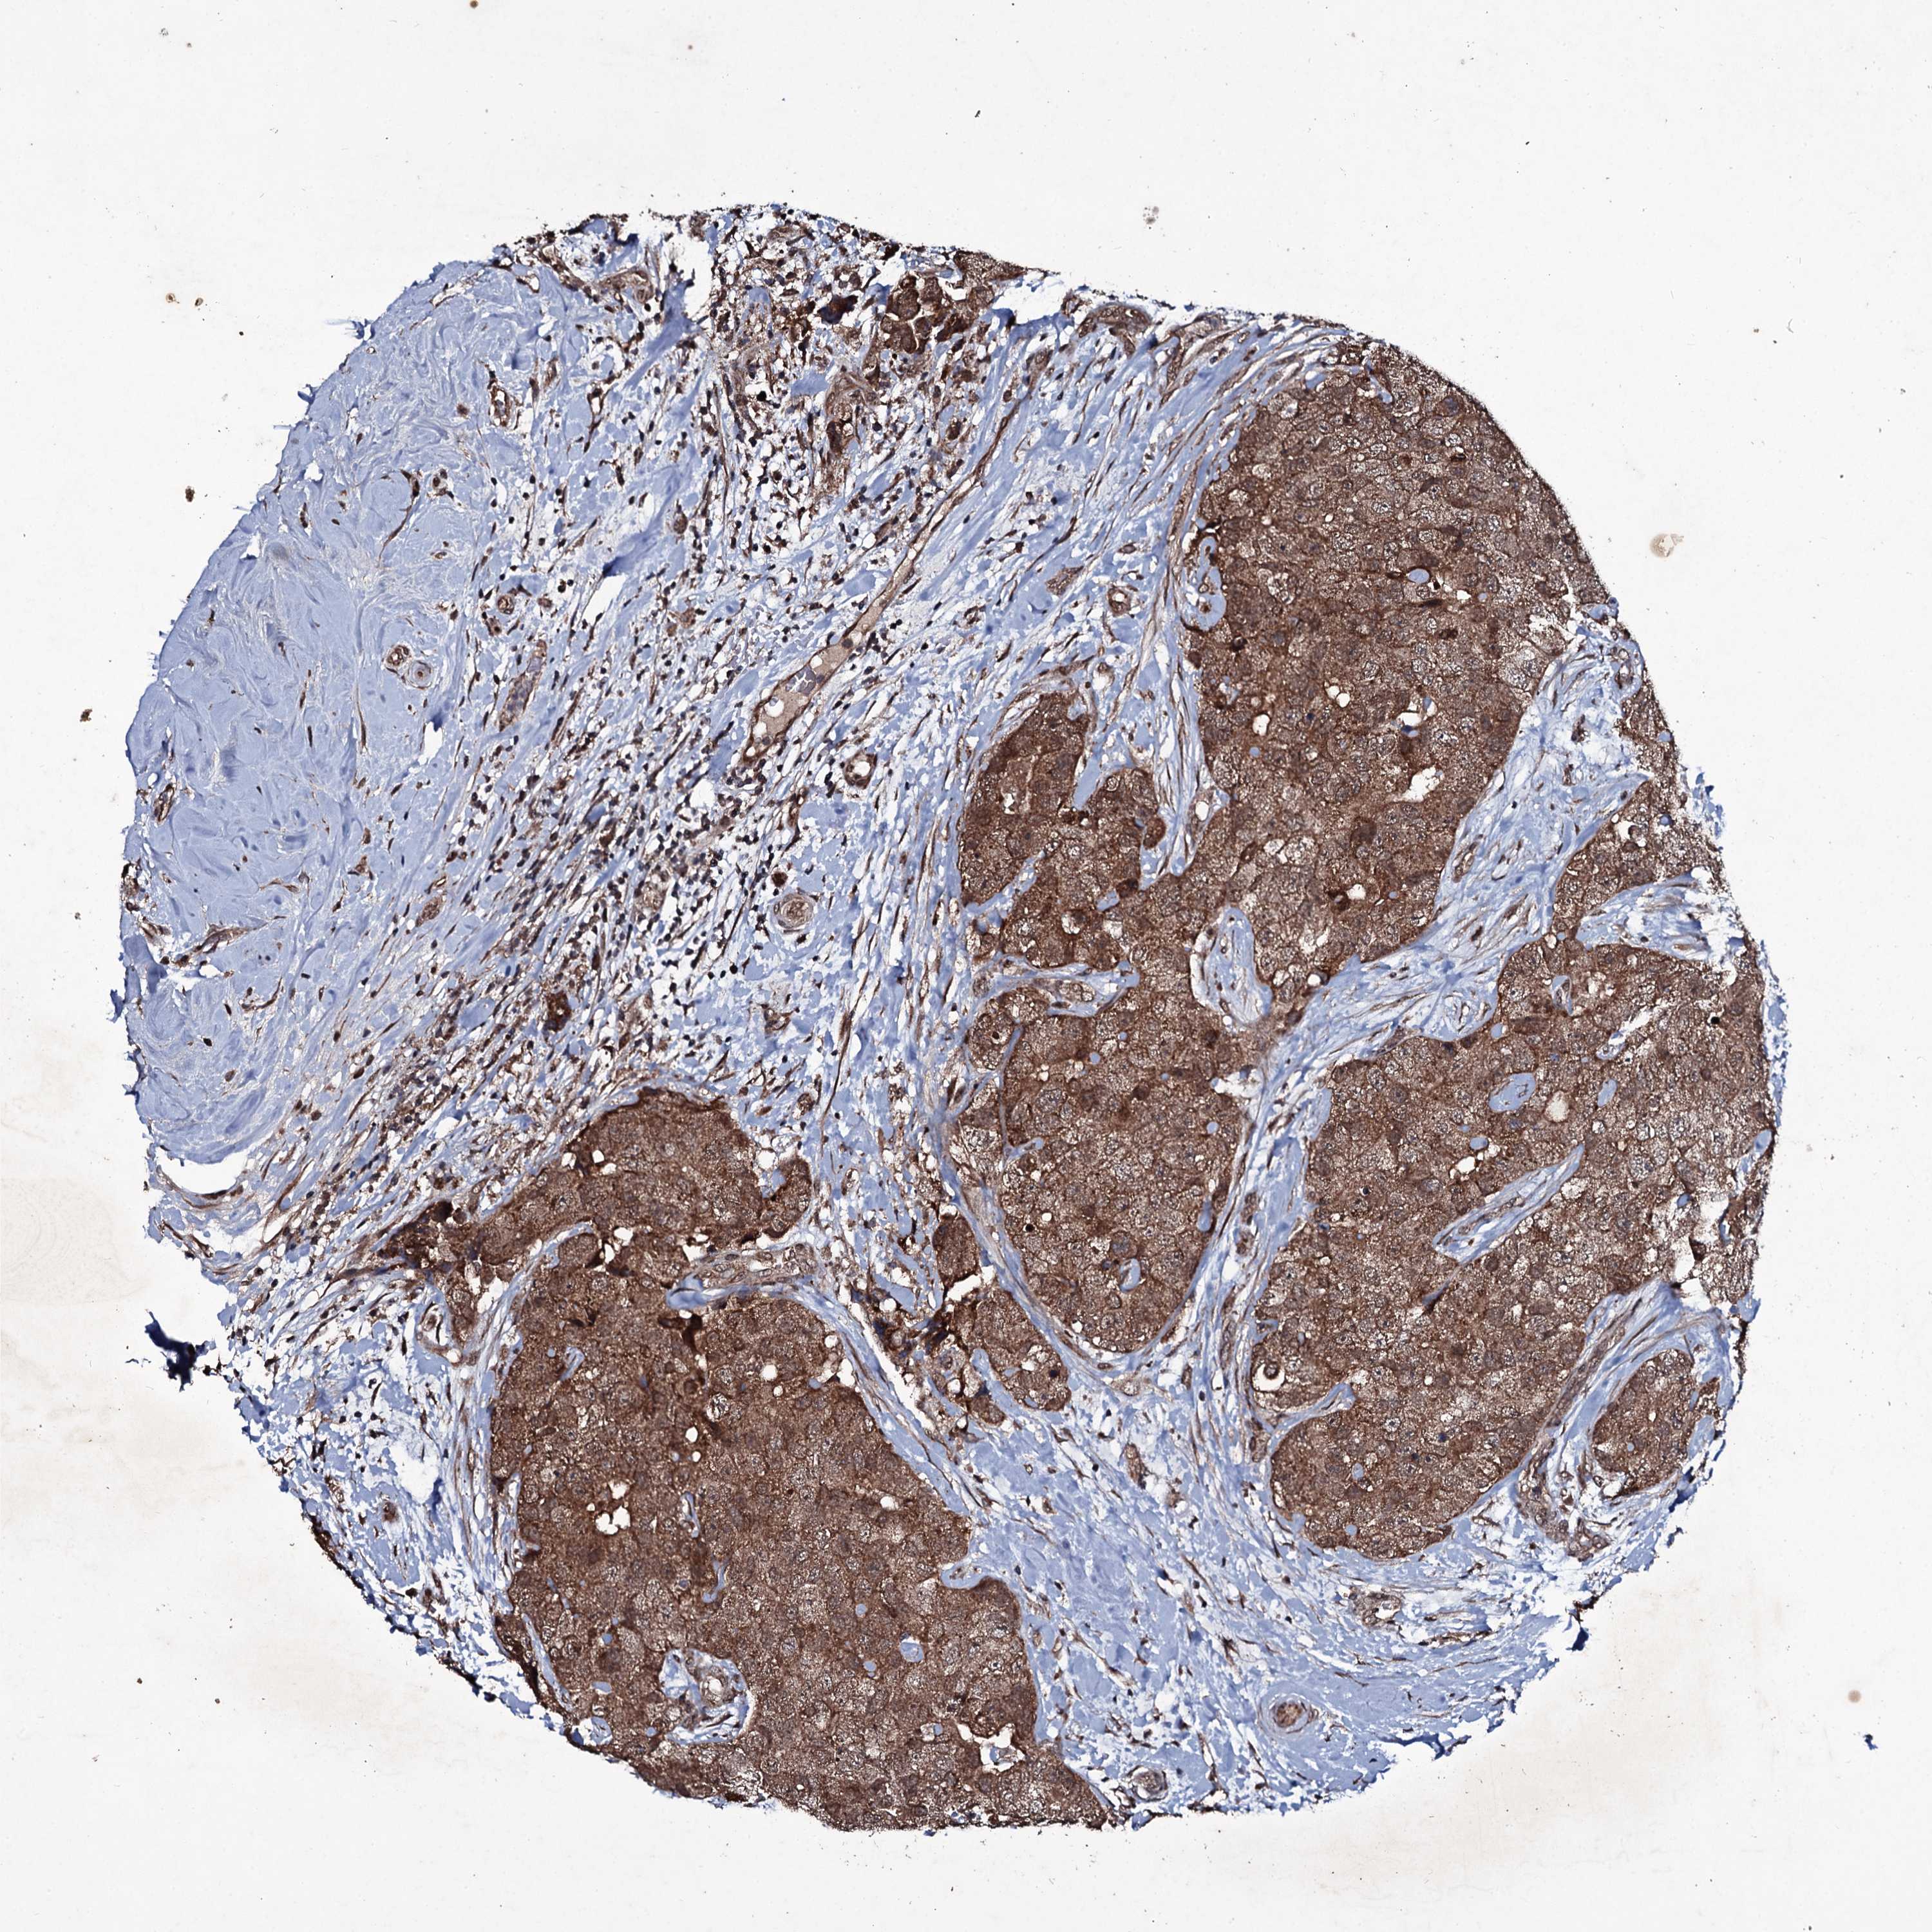

CANCER BREAST CANCER Show tissue menu

BRCA TCGA BRCA VALIDATION PROTEIN EXPRESSION

ANTIBODIES

AND

VALIDATION